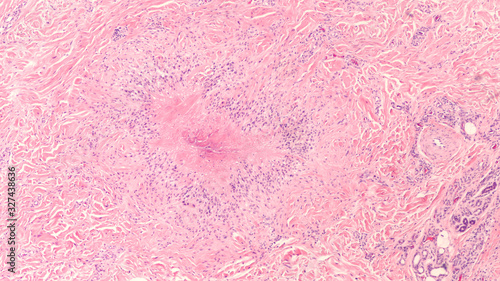

Mikrofotografi - Plakater, Poster, Billeder på lærred